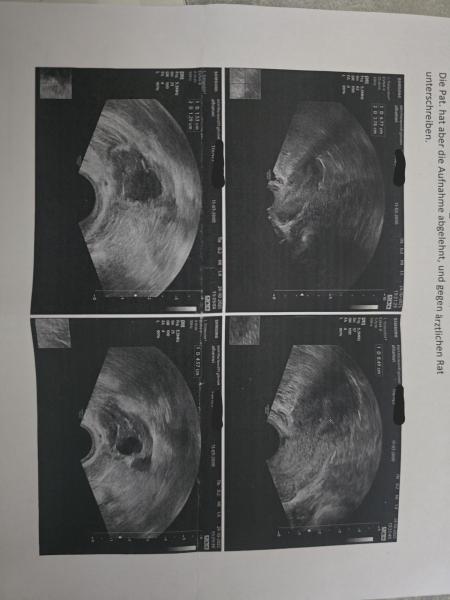

Hallöchen, ich bin langsam echt verzweifelt. Ich hatte am 29.09. ganz normal und pünktlich meine Periode, wegen mehrerer Anzeichen wie teilweise Übelkeit, Stimmungsschwankungen und Brustschmerzen habe ich dann aber am 20.10. Nachmittags deutlich positiv getestet. Ich muss dazu sagen, das ich am 13.10 und am 20.10. Vormittags leichte braune schmierblutungen mit Gewebestückchen hatte. Ich habe also am 21.10. Direkt einen Termin beim Frauenarzt gehabt, war bei einem anderen Arzt, weil meine Ärztin keine Termine mehr frei hatte. Dieser hat US gemacht und nichts gesehen. Eierstöcke waren unauffällig und die Gebärmutter auch. Keine aufgebaute Schleimhaut. Blut wurde abgenommen. Einen Tag später rief mich meine normale Ärztin an und sagte der HCG war bei 3200. Sollte also direkt nochmal den nächsten Tag in die Praxis kommen. Sie hat wieder nichts gesehen. Nochmal Blut abgenommen. Nächsten Tag rief sie mich wieder an und meinte der HCG war bei 5600 und ich sollte bitte so schnell wie möglich vorbeikommen, denn man müsste nun was sehen, ansonsten müsste ich ins Krankenhaus, Verdacht auf ELSS.... Ich bin den nächsten Tag hin und sie hat Vaginal und auch von Oben ein US gemacht. Wieder keine aufgebaute Schleimhaut. Sie hat in der Praxis gesagt, es KÖNNTE im rechten Eileiter sitzen, sie ist sich aber nicht sicher. Also habe ich eine Notfallüberweisung ins Krankenhaus bekommen. Ich bin im Auto komplett zusammen gebrochen und hab erstmal 10 min geheult weil ich panische Angst vor OPs habe, noch nie über Nacht im KH war, geschweige denn eine Vollnarkose hatte. Ich bin dann gegen Mittag mit meinem Freund ins Krankenhaus in die Notaufnahme gefahren. Habe Blutabgenommen, habe die Untersuchungen einfach über mich ergehen lassen. Ich war komplett fertig mit den Nerven und hatte höllische Angst Operiert werden zu müssen. Dann saß ich bei der Ärztin im Zimmer und sie machte verschiedene Untersuchungen und auch einen Vaginalen Ultraschall. Das einzige was sie gesehen hat ist eine 15mm große Zyste am rechten Eierstock. Der rest sah komplett unauffällig aus. Die hat mich am Bauch und Vaginal komplett abgetastet. Ich hatte keinerlei Schmerzen oder ähnliches. Sie hat zum derzeitigen Punkt eine ELSS ausgeschlossen. Die wollten mich stationäre aufnehmen, aber ich habe es abgelehnt und gegen ärztlichen Rat unterschrieben. Der HCG im KH war bei 5200 und auch wieder keine hoch aufgebaute Schleimhaut. Ich habe sie mehrfach gefragt, ob wenn ich jetzt gehe da irgendwas platzen kann über Nacht oder irgendwas passieren kann, sie hat gesagt nein das kann nicht passieren. Sobald ich Schmerzen bekomme, oder irgendwelche anderen beschwerden soll ich sofort nochmal vorstellig werden. Ansonsten sollte ich am Montag zum Frauenarzt fahren um den HCG zu kontrollieren ob er weiter fällt, dann ist alles gut meinte sie. Ich muss dazu sagen das ich vor 2 Jahren auch schon 3 frühaborte gehabt habe, wo man auch nie etwas gesehen hat, aber da war mein HCG wert nie über den 1000er bereich und es hat immer mit einer Abbruchsblutung geendet. Ich habe jetzt trotzdem panische Angst, das es doch eine ELSS ist und ich trotzdem irgendwie noch Operiert werden muss und nochmal ins Krankenhaus muss. Ich hoffe der HCG fällt weiter und ich kriege irgendwann einfach meine Blutung... Hatte jemand sowas ähnliches schonmal? Kann mir jemand seine Erfahrungen mitteilen und mich evtl beruhigen? Ich sollte laut app am 30.10. meine Periode kriegen, aber da ich ja keine hoch aufgebaute Schleimhaut habe, denke ich das sie da nicht kommen wird... Ich hänge mal die US Bilder von gestern aus dem Krankenhaus mit dran, vielleicht kennt sich da jemand ein bisschen aus.